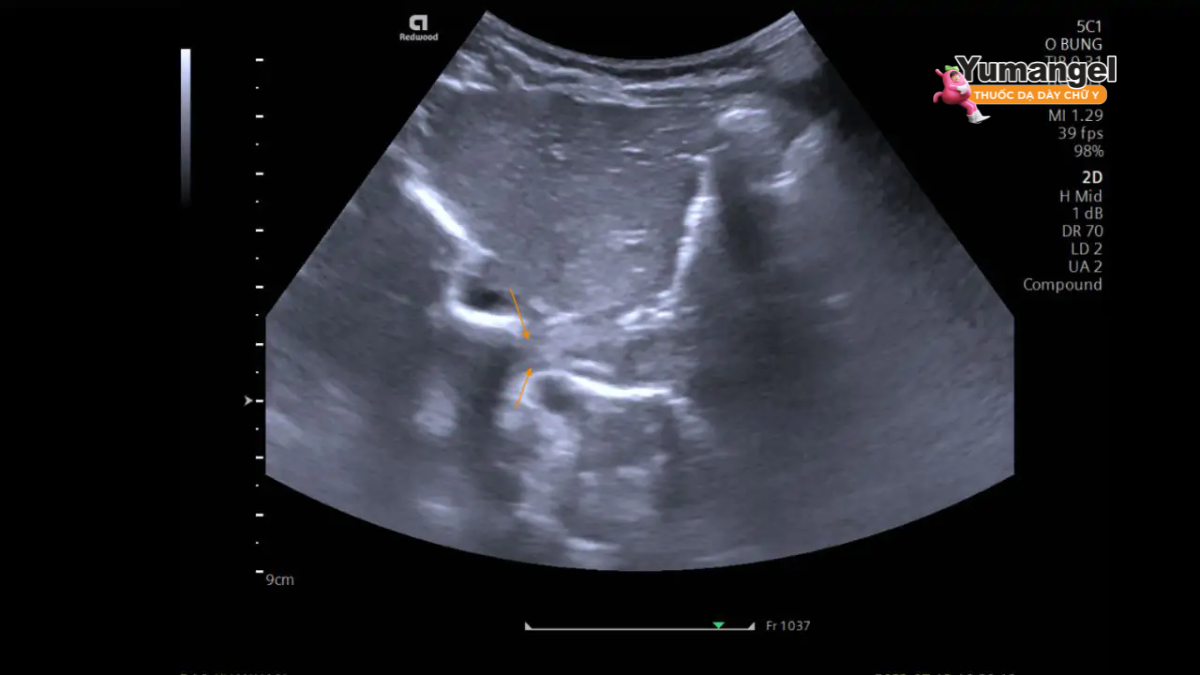

III. Giải đáp: Siêu âm có phát hiện trào ngược dạ dày không?

Đây là câu hỏi trọng tâm. Dựa trên các nghiên cứu và thực tế lâm sàng, câu trả lời là: Siêu âm có thể có vai trò nhất định nhưng không phải là phương pháp tối ưu để chẩn đoán toàn diện bệnh trào ngược dạ dày thực quản.

- Một số nghiên cứu (đặc biệt ở trẻ em) cho thấy siêu âm có độ nhạy trong việc phát hiện trực tiếp luồng trào ngược từ dạ dày lên thực quản tại thời điểm siêu âm (1).

- Siêu âm có thể ghi nhận được các triệu chứng xảy ra đồng thời với luồng trào ngược (ví dụ: ho, khó chịu, nôn trớ…), giúp liên kết triệu chứng với hiện tượng trào ngược (gọi là “symptomatic reflux”).

- Khó đánh giá niêm mạc: Siêu âm không thể quan sát trực tiếp và chi tiết bề mặt niêm mạc thực quản, dạ dày. Do đó, nó không đánh giá chính xác được mức độ viêm, các vết loét nông hay sâu, hoặc các tổn thương tiền ung thư như Barrett thực quản. Đây là hạn chế lớn nhất về tính chính xác trong chẩn đoán GERD.

- Phụ thuộc vào thời điểm: Chỉ phát hiện được luồng trào ngược nếu nó xảy ra đúng lúc đang siêu âm.

Kết luận: Siêu âm có thể hữu ích để phát hiện sự kiện trào ngược hoặc các vấn đề cấu trúc khác, nhưng không đủ để chẩn đoán đầy đủ mức độ và biến chứng của GERD. Nó không thay thế được nội soi trong việc đánh giá tổn thương niêm mạc.